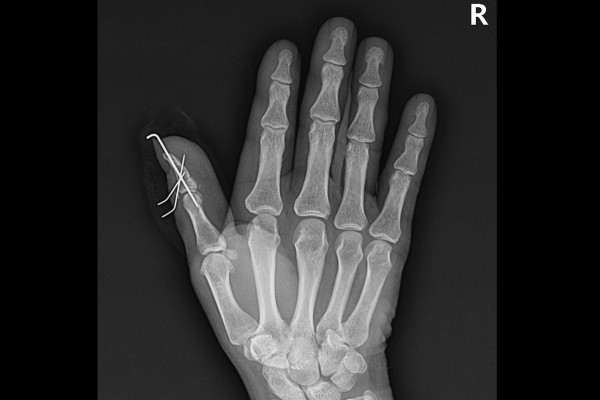

수술 후 X-RAY를 보면 뼈가 잘 고정된 것이 확인됩니다.

추후에 핀 제거 후 찍은 X-RAY를 확인했을 때 원래 위치로 깔끔하게 잘 정복된 것이 확인됩니다.